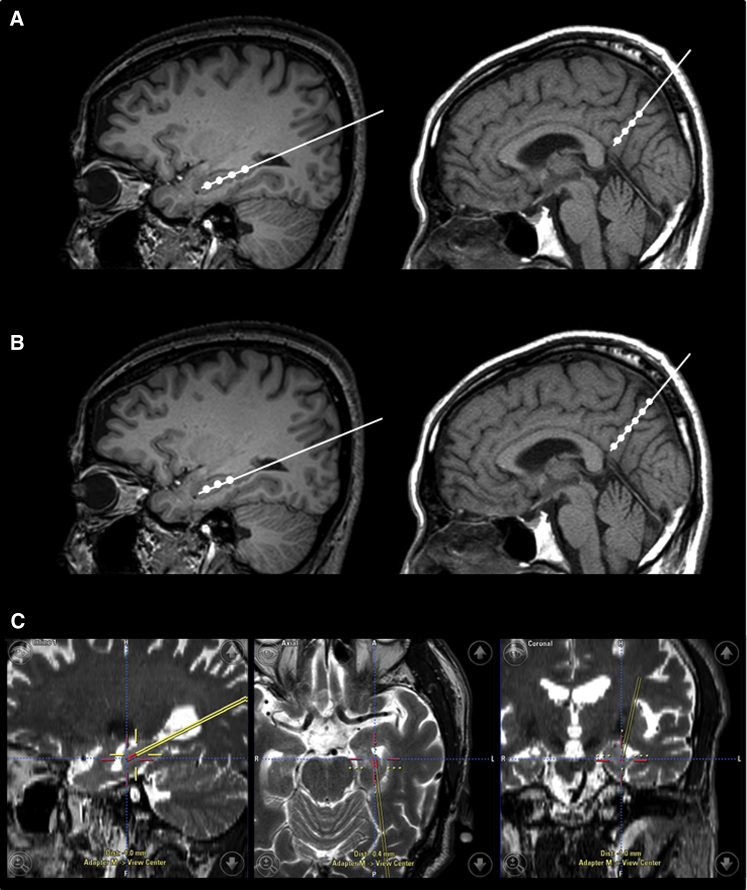

臍帶間充質(zhì)干細胞的立體定向給藥

- (A)術(shù)中導航引導 hUCB-MSC 立體定向給藥。在縮回套管的同時,沿插入軌跡將 hUCB-MSC 注射到左右海馬和右楔前葉的四個部位(間隔 5 毫米)

- (B)然而,在九名患者中,有六名患者的第四次注射位于側(cè)腦室顳角,這可能是由于海馬嚴重萎縮所致。在這些情況下,省略的劑量被注射到右楔前葉,導致每個海馬有三個注射部位,右楔前葉有六個注射部位。

- (C)將 hUCB-MSC 立體定向注射到左海馬的示例